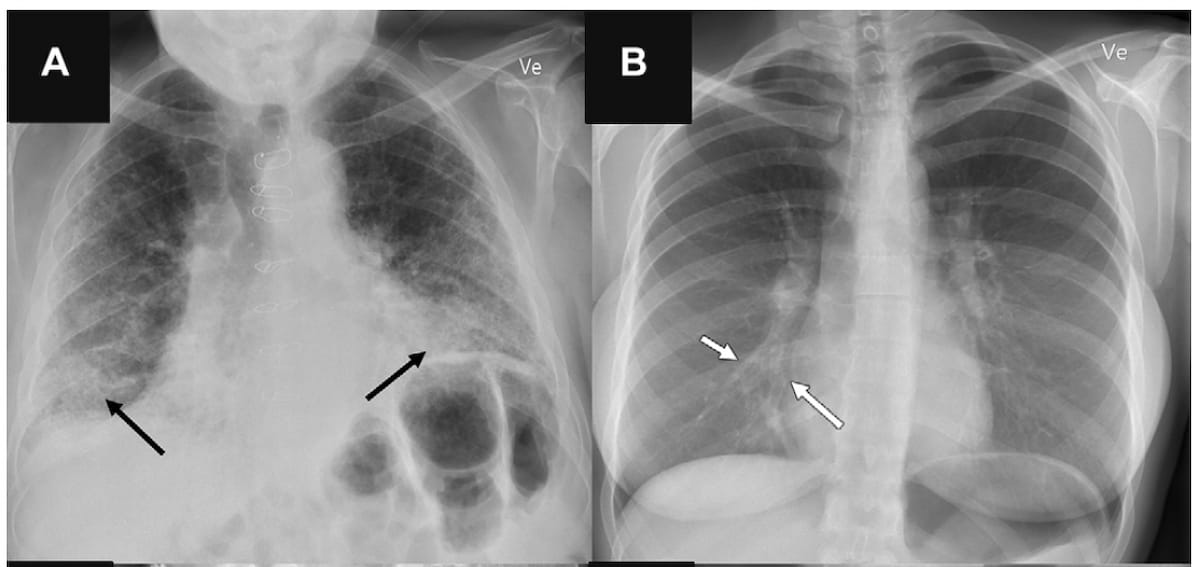

In a multicenter study examining four commercially available artificial intelligence (AI) software products for chest X-rays in over 2,000 patients, researchers found sensitivity rates ranging between 33 to 61 percent for vague airspace disease and 9 to 94 percent for small pneumothorax and pleural effusion.

In a study of over 1,500 patients, researchers found that an emerging artificial intelligence (AI) modality had significantly higher sensitivity rates for abnormal posteroanterior chest radiographs and critical finding radiographs than radiology reports.